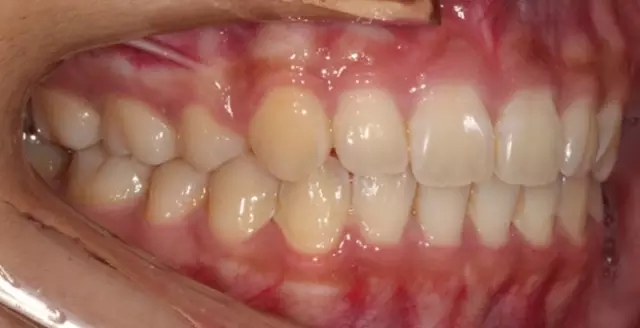

Damon 病例分享:安氏 II 類二分類露齦笑的矯治(董一磊)

治療前后對比